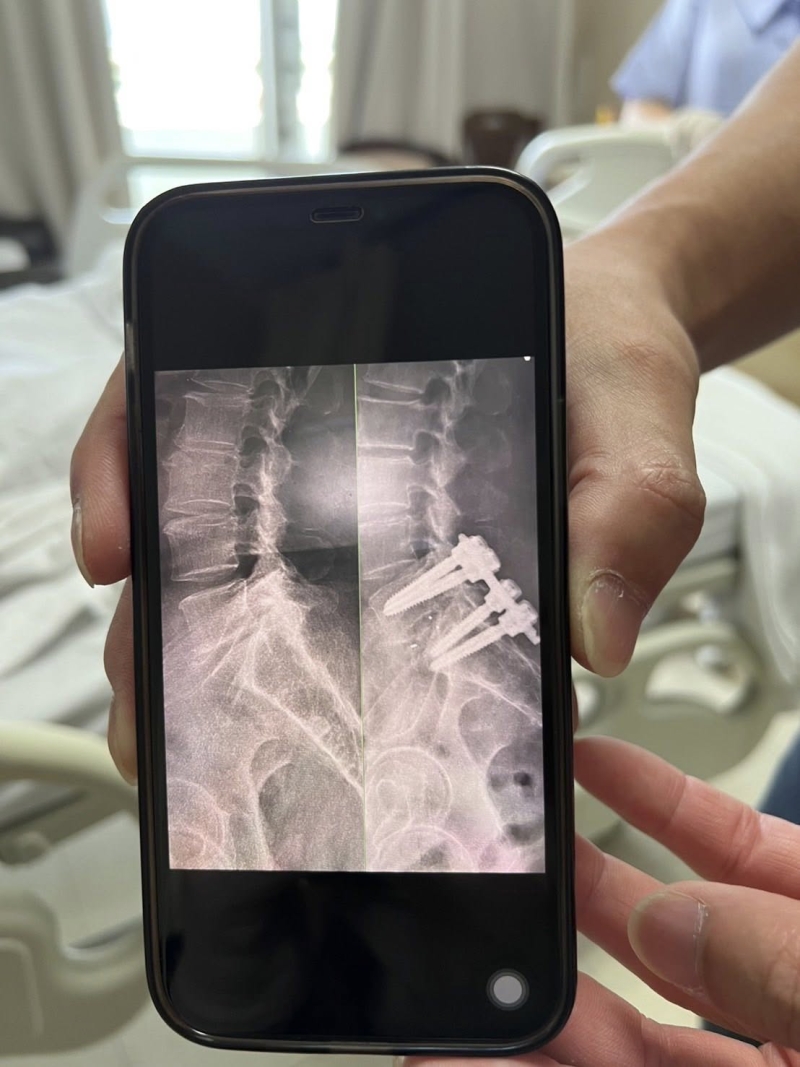

สาเหตุคือมันปวดแบบที่เรียกว่าเจ็บปวดมากถึงมากที่สุด เข่าขวาเจ็บแบบกระดูกมันเกยกัน เข่าซ้ายเจ็บ ก้นซ้ายเจ็บปวดร้าวลงขาถึงข้อเท้า แข้งและน่องดำปี๋ทั้ง 2ข้าง เส้นเลือดดำเส้นเลือดแดงแต่มันดำ กระจายไปทั่ว ข้อเท้าบวมทั้ง 2ข้าง ไม่สามารถยืนตัวตรงได้เลย ต้องก้มตัวแล้วใช้แขนเท้าโต๊ะหรือขอบอ่างทุกกิจกรรมต้องใช้เก้าอึ้พลาสติคตามตลอดเพราะต้องนั่งพักทุกการเดิน 3ก้าว จากผลเอกซเรย์และ MRI คุณหมอบอกว่ามันมีปัญหาที่กระดูกสันหลัง L 5กับS1

เดือนเมษายน 2568คุณหมอบอกว่าต้องแก้ปัญหาที่หลังก่อนแล้วค่อยจัดการเรื่องเข่า แต่ใจเราอยากผ่าเข่าก่อน คุณหมอยืนยันต้องผ่าหลังก่อนให้เวลาตัดสินใจ 1เดือนสรุปนัดผ่าตัดกระดูกสันหลังที่มีปัญหา วันที่ 6มิถุนายน 2568ให้อดอาหารและน้ำ 7โมง เช้า ให้ถึงโรงพยาบาล11โมงเพื่อผ่าตัดเวลา 15.00น. ผ่าตัดนานมากจากที่กำหนดไว้ 2ชั่วโมง